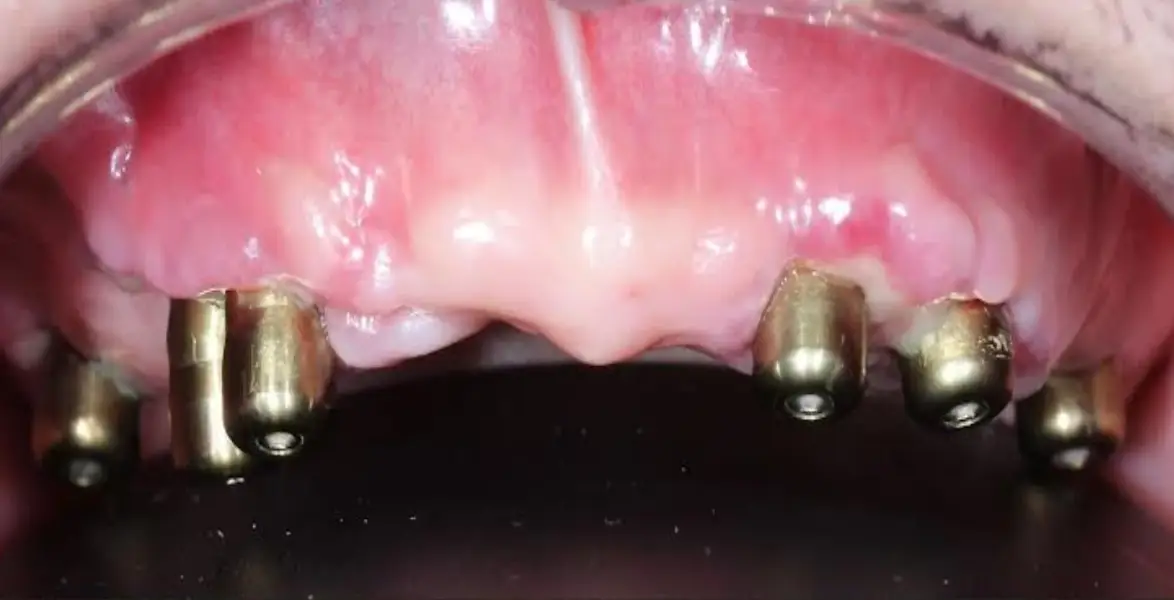

Procedure Techniques of All-On-6 Dental Implants

- First Consultation & Evaluation – Taking an in-depth assessment by using digital scans to determine dental health, bone density, & suitability of solution

- Placement of Implant – 6 best quality titanium-made implants are settled at tactically measured angles for supreme stability